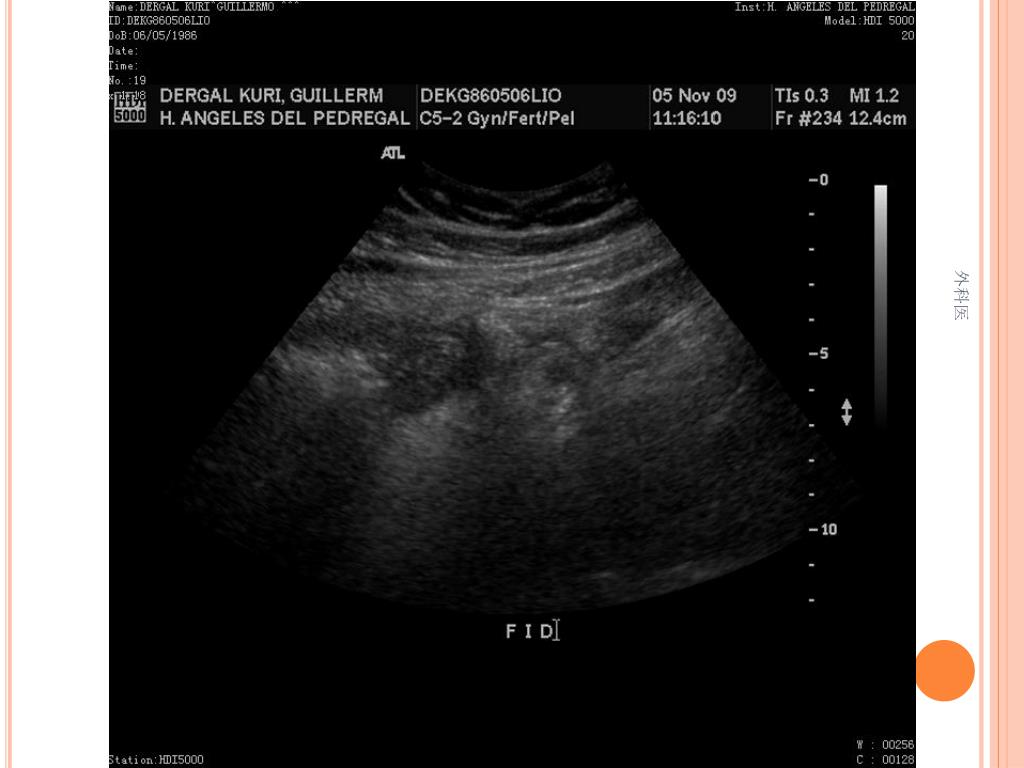

44. Tips • Leucocitos Mas de 20000/ml • Mas de 20% de la apéndices no se llenan con el bario por enema. • USG sensibilidad del 85% y Especificidad de mas 90% para Apendicitis Aguda. • TAC de Abdomen cortes de 5mm, sensibilidad y especificidad del 90% para dolor abdominal. • Analisis de 75000, taza de apendice negativa de 6% Hombres y 13% Mujeres 外科医